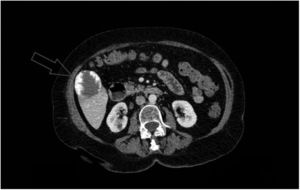

Mujer de 75 años, en estudio por un cuadro de anemia microcítica-hipocrómica de 3 años de evolución, tratada en varias ocasiones con hierro oral y transfusiones sanguíneas. Presentaba afección hemorroidal y deposiciones oscuras en relación con la terapia férrica. El último control analítico reveló Hb 10g/dl, VCM 72f/l, hierro 47μg/dl, ferritina 250ng/ml, vitamina B12 378pg/ml y ácido fólico 6ng/ml. En la endoscopia digestiva alta se objetivó gastritis eritematosa leve con gran hernia de hiato por deslizamiento, mientras que la colonoscopia mostró hemorroides internas y colón espástico, sin signos de sangrado activo en ambas pruebas. Ante la sospecha de sangrado oculto se realizó gammagrafía con hematíes marcados con 99mTc-pirofosfato de estaño (figs. 1A y B) y SPECT/TC abdominal (figs. 1C y D), revelando captación endoluminal del trazador en extremo distal del colon ascendente compatible con hemorragia de bajo débito. Adicionalmente, se identificó un área hipercaptante redondeado y bien delimitado en segmento V hepático correspondiente a hemangioma. En la TC abdominal con contraste iv (fig. 2) se objetivó el patrón típico de captación progresiva centrípeta que apoyaba el diagnóstico de hemangioma hepático, sin evidencia de alteraciones en asas intestinales. Fue tratada con 100mg hierro-trivalente/2 semanas y se repitió estudio esófago-gastro-duodenal, tránsito intestinal con bario y colonoscopia, sin detectarse alteraciones significativas. Actualmente la paciente se encuentra asintomática, mostrando en los controles analíticos valores de Hb estables.